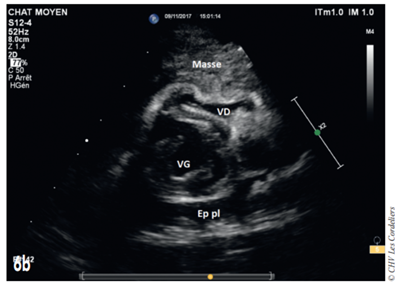

Fig 3a

Fig. 3a – Échocardiographie du 23/09/2017 (J+42 jours) : mise en évidence d’une masse hétérogène comprimant la veine cave caudale (VCC) et l’atrium droit (AD) ; AG (atrium gauche) ; Ao (aorte) ; Art Pul D (artère pulmonaire droite) ; Art Pul G (artère pulmonaire gauche) ; TP (tronc pulmonaire) ; VD (ventricule droit).

Fig 3b

Fig. 3b – Échocardiographie du 23/09/2017 (J+42 jours) : mise en évidence d’un épanchement pleural (Ep pl) ; VG (ventricule gauche) ; VD (ventricule droit).

J+42 jours : malgré le bon état général, la dyspnée persiste. L’échocardiographie (Fig. 3a et 3b) montre une masse pulmonaire maintenant cavitaire s’étendant jusque dans le médiastin crânial et associé à un épanchement pleural.